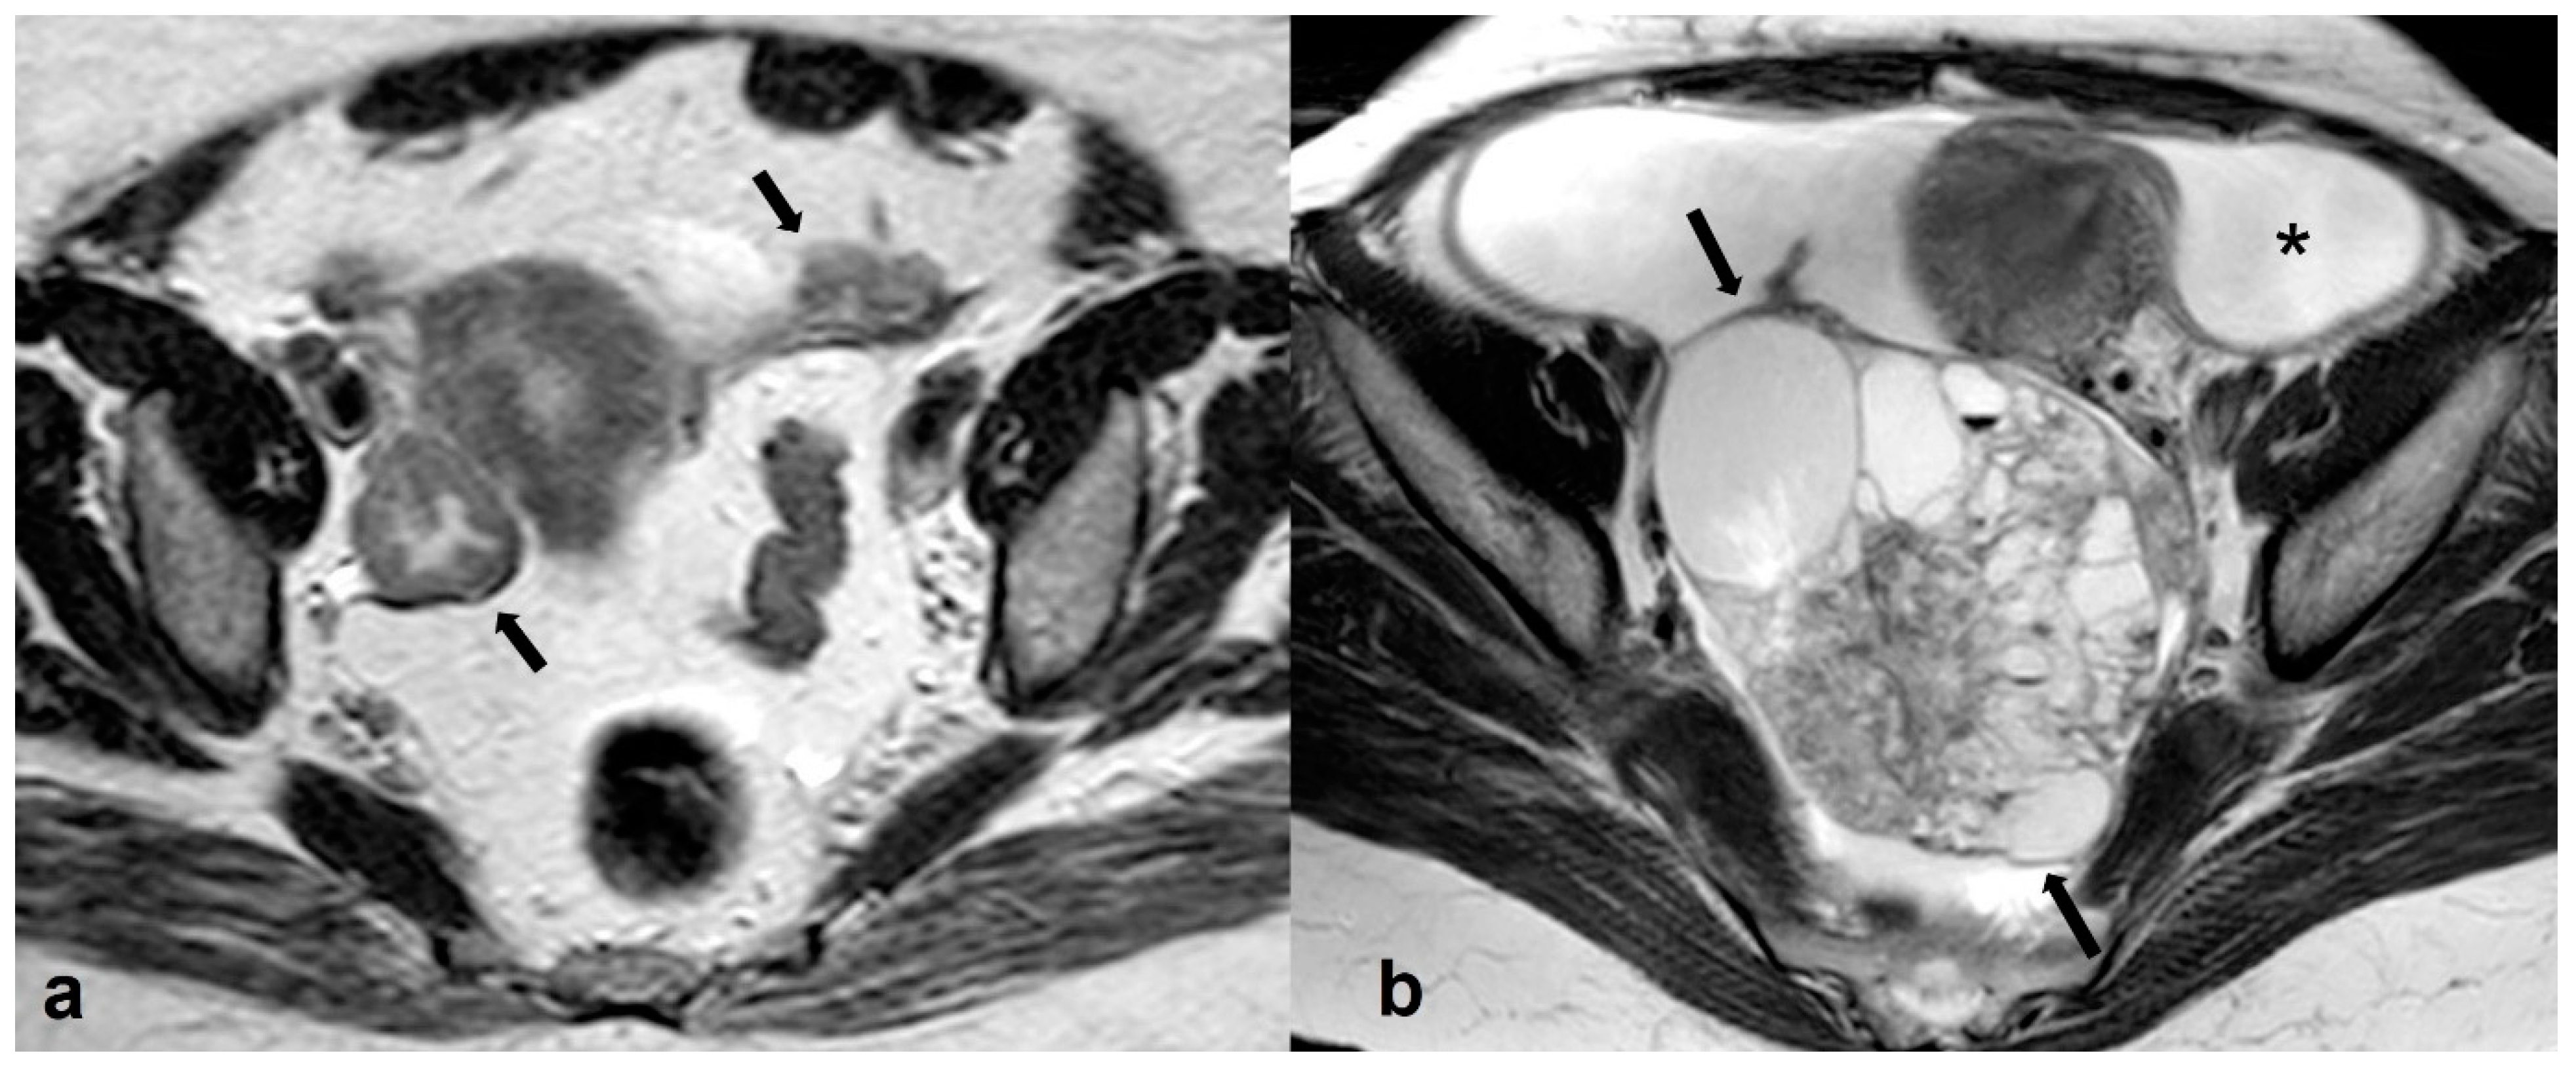

2.3.5. Metastases

2.4. Adolescence-Germ Cell Tumors